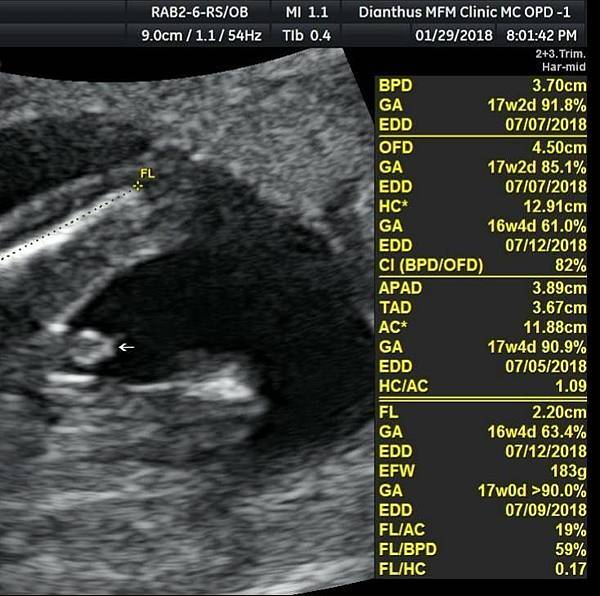

// 20180307超音波告訴我的事 //

以前完全看不懂超音波,一坨坨的黑白影,沒人說還真沒人看得懂。